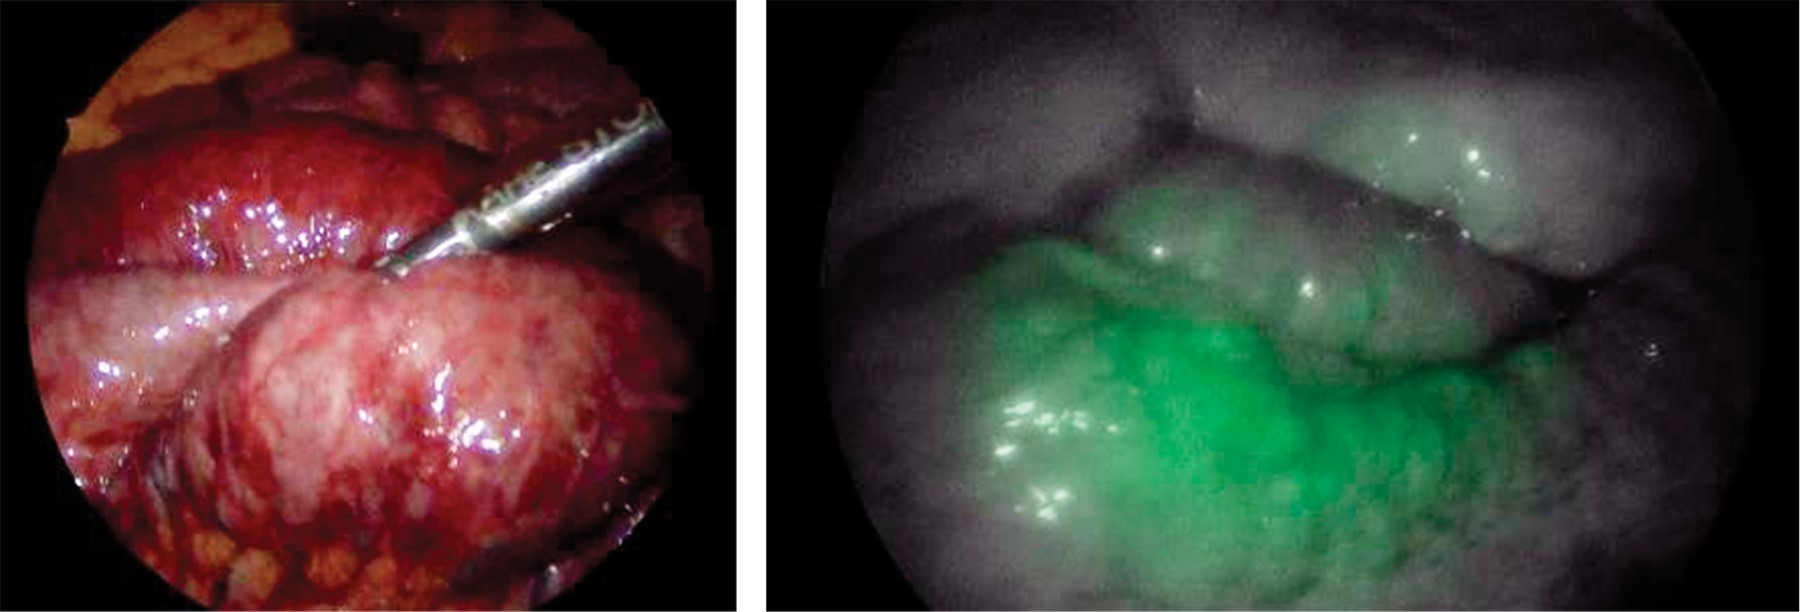

Intestinal ischemia and indocyanine green fluorescence: its use as a therapeutic tool, apropos of a clinical case

Introduction: An acute case of intestinal ischemia is a surgical emergency that could lead to abdominal sepsis, mesenteric or bowel infarction or even death. Amongst the new available measures to make an early diagnosis is the use of indocyanine green which has been used in hepato-biliary and oncologic surgery amongst others. However, there are only a few reports in the literature about its use in intestinal ischemia. Clinical case: This is the case of a 33-year-old female with abdominal pain and tomographic findings of an extense filling defect involving venous ileal branches, the superior mesenteric vein and partially the portal vein secondary to thrombosis and changes in the small bowel suggesting bowel ischemia. An exploratory laparoscopy was performed using indocyanine green to evaluate intestinal perfusion ruling out ischemia or necrosis. After further evaluation and with a multidisciplinary management to rule out prothrombotic states a second-look laparoscopy was performed using indocyanine green corroborating an adequate intestinal perfusion and intestinal viability. Her post-operative evolution was favorable and was discharged home. Conclusion: This case exemplifies how the use of indocyanine green has useful applications in the management of intestinal ischemia and can avoid unnecessary bowel resections.

Figure 1